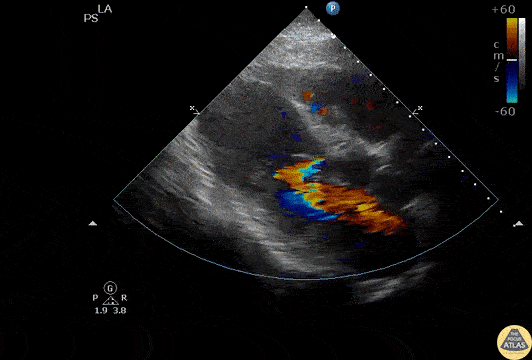

A parasternal long axis view reveals a ventricular septal defect in a patient presenting with symptoms of GERD, an elevated troponin, and an EKG indicative of myocardial infarction. Image courtesy of Robert Jones DO, FACEP @RJonesSonoEM Director, Emergency Ultrasound; MetroHealth Medical Center; Professor, Case Western Reserve Medical School, Cleveland, OH View his original post here